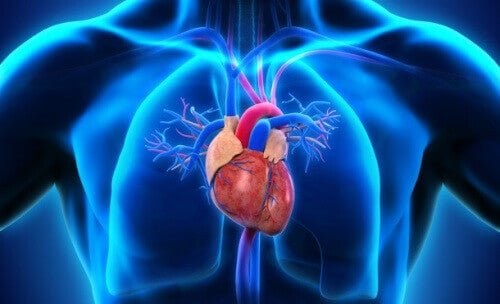

In un cuore normale, il sangue segue questo percorso: corpo-cuore-polmoni-cuore-corpo. Quando la persona presenta un tronco arterioso comune, il sangue messo in circolo dal cuore non segue questo percorso naturale.

In questo caso, il cuore non possiede 4 compartimenti correttamente separati, ma solo una cavità. Di conseguenza, non ci sono atri né ventricoli che separano il sangue in base alla sua origine e destinazione. C’è solo un’arteria comune, senza un percorso specifico per il sangue ricco di anidride carbonica e per il sangue ossigenato.